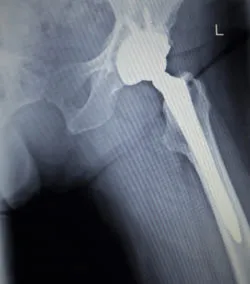

La période de réclamation dans le règlement du recours collectif contre les prothèses Stryker s’est ouverte le 30 mars 2020, donnant droit à des milliers de dollars d’indemnités à ceux qui ont reçu la prothèse de hanche modulaire Rejuvenate de Stryker prétendument défectueux.

Les membres du recours collectif comprennent les personnes qui ont reçu une prothèse de hanche modulaire Rejuvenate de Stryker au Canada, ainsi que les membres de leur famille et/ou leur succession si nécessaire.

Le recours collectif contre Stryker allègue que des prothèses de hanche défectueuses ont été implantées chez les membres du groupe et que le système de hanche modulaire Rejuvenate de Stryker a fait l’objet d’une publicité mensongère comme étant un implant de hanche non métal sur métal.

Le recours collectif a souligné que les prothèses de hanche sont utilisées depuis plus de 40 ans et peuvent être un moyen efficace pour traiter les maladies et les blessures de l’articulation de la hanche. Cependant, les prothèses de hanche métal-métal ont tendance à causer des dommages après avoir été implantées. Selon la plainte, les composants métalliques se frottent, se fissurent et se corrodent, dégageant du métal dans les tissus. Des problèmes de relâchement prématuré, de mauvais alignement, de fracture, de dislocation et d’échec ont également été liés aux prothèses métal sur métal, selon les demandeurs.

Malgré ces problèmes, connus depuis les années 1970, Stryker a conçu un système de prothèse de hanche utilisant des composants métalliques, selon la plainte. Le système modulaire de hanche Rejuvenate de Stryker comprend des composants de cou et de tige modulaires en métal. Ces composants se frottent les uns aux autres, causant des problèmes aux patients, selon les demandeurs.

Le recours collectif contre Stryker allègue en outre que la prothèse de hanche modulaire Rejuvenate a été commercialisé de manière trompeuse comme un produit non métal sur métal parce que le produit n’a pas de tête fémorale et de revêtement métallique. Cependant, les composants métalliques de l’appareil auraient frotté, selon la plainte, causant un préjudice aux demandeurs et aux membres du groupe proposé.